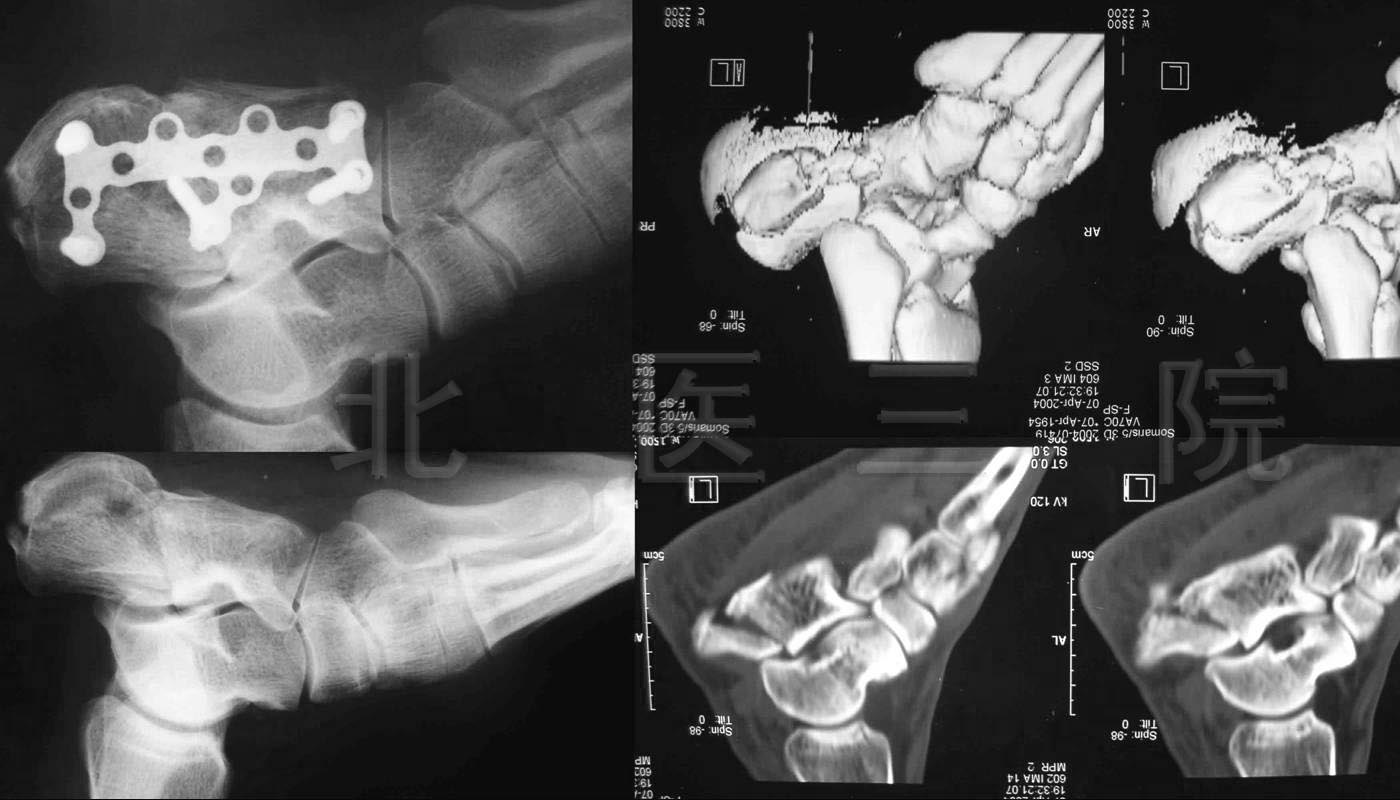

1.女,65岁,肱骨髁间粉碎性骨折,术后肘关节功能大部分恢复

2.前臂双骨折,交锁髓内钉固定

3.桡骨末端掌侧Barton骨折

4.男,35岁,车祸致多发创伤

1)股骨上端骨折

2)胫腓骨下端粉碎性骨折

3)L1、L2骨折

5.女,66岁,外伤致股骨下端骨折,行股骨逆行交锁髓内

钉固定术

6.女,43岁,车祸致胫骨平台骨折

7.男,49岁,胫腓骨骨折,径胫骨髓内钉固定+腓骨钢板固定

8.男,44岁,高处坠落伤致左髋臼、骨盆骨折

9.男,55岁,高处坠落伤致跟骨骨折

10.C6陈旧性骨折脱位

男,23岁,70天前车祸伤,当时有昏精迷史,2天后苏醒,

感觉颈部疼痛,右前臂与右手掌尺侧感觉过敏,左手指不能

活动,双下肢感觉活动正常保守治疗后症状加重,转我院手

术治疗症状缓解

11.L3爆散性骨折脱位

男,38岁,L3爆散性骨折脱位伴尾神经完全损伤3周入院

术后可乘坐轮椅